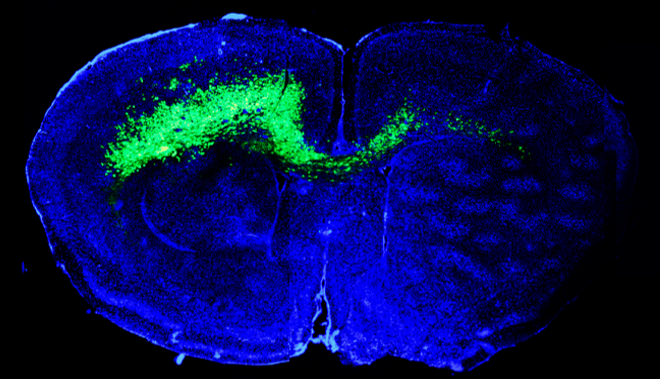

The burgeoning field of cancer neuroscience fuses the tenets of cancer biology and neuroscience to provide new avenues for improving our understanding of brain cancer and ultimately pioneer new treatments for patients. To find new solutions for brain cancer patients, our team of world-class neurosurgeons and neuroscientists created the Center for Cancer Neuroscience. As pioneers in this nascent field, our team discovered that brain tumors use the nervous system’s native neural network as a “highway” to spread to other parts of the brain and hijack immune cells to hide from the immune system. Leveraging our transdisciplinary expertise our team will work to uncover the causes and identify therapeutic targets leading to better treatments and preventive approaches for brain tumors.